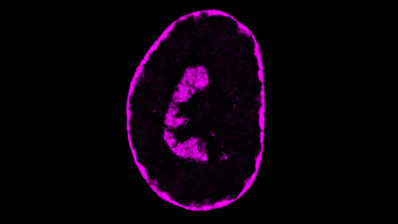

El càncer necessita energia per moure’s